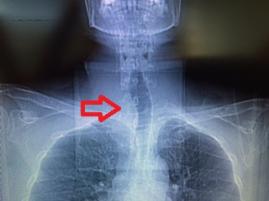

- Bu belirtiler sizde varsa tiroid hastalığınız olabilir !!